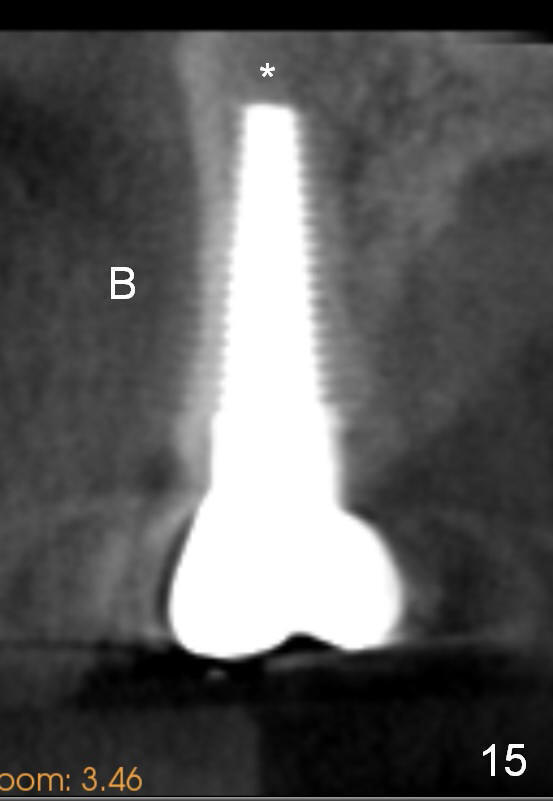

Eight months post cementation, CBCT shows periapical infection of the neighboring teeth (Fig.14 *). There is still apical bone for a longer implant (Fig.14 green line, Fig.15 *). The implant functions 1.5 years post cementation. When the implant at the lower bicuspid fails, the patient reveals that he is a diabetic. The latter is the main reason of delayed healing.